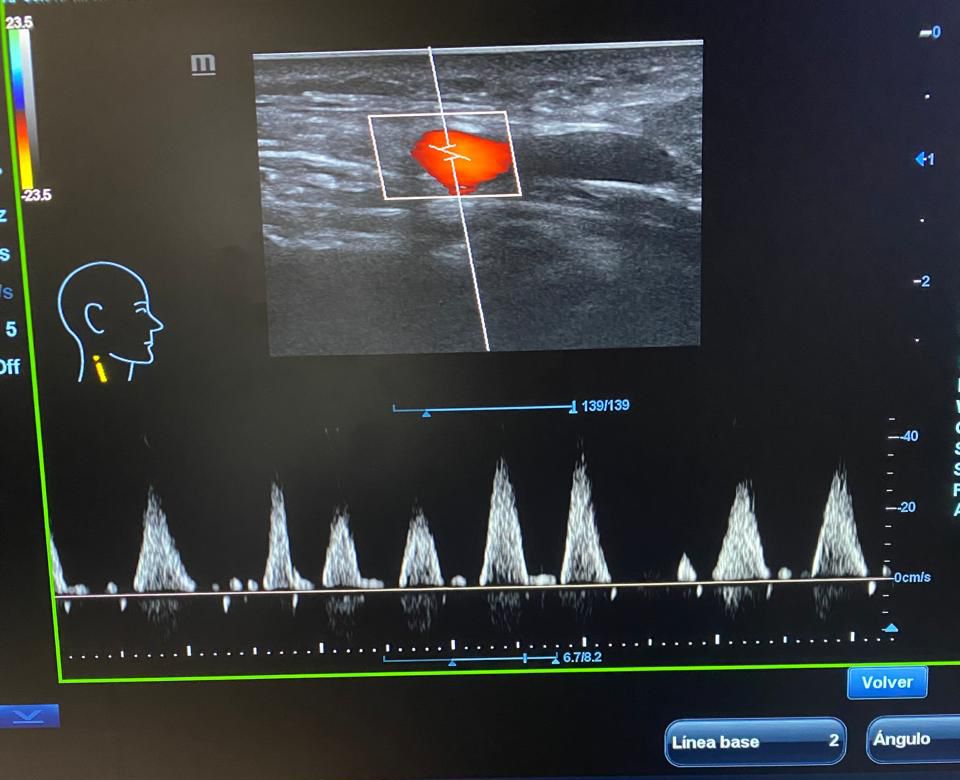

El Hospital Municipal Dr. Luis Espaillat informó la ampliación de sus servicios diagnósticos con la incorporación de la sonografía Doppler, una herramienta de gran importancia para la detección y seguimiento de diversas condiciones de salud relacionadas con la circulación sanguínea.

La dirección del centro de salud detalló que, además del nuevo servicio de Doppler periférico arterial y venoso, así como Doppler carotídeo, el hospital pone a disposición de la comunidad una amplia gama de estudios sonográficos que incluyen: abdominal, obstétrica, ginecológica (transvaginal y suprapúbica), de mama, tiroides, próstata (transrectal y transabdominal), testicular, de partes blandas y músculo esquelético.

Los estudios de Doppler y músculo esquelético estarán disponibles los lunes, miércoles y viernes en horario matutino, mientras que el resto de las sonografías se realizarán todos los días.